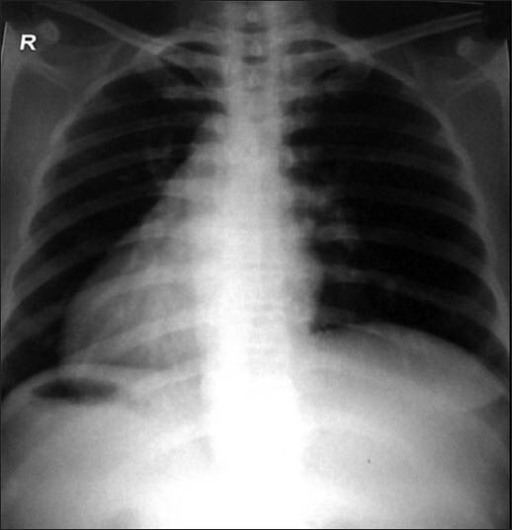

Puzzle 24

What's the Diagnosis?